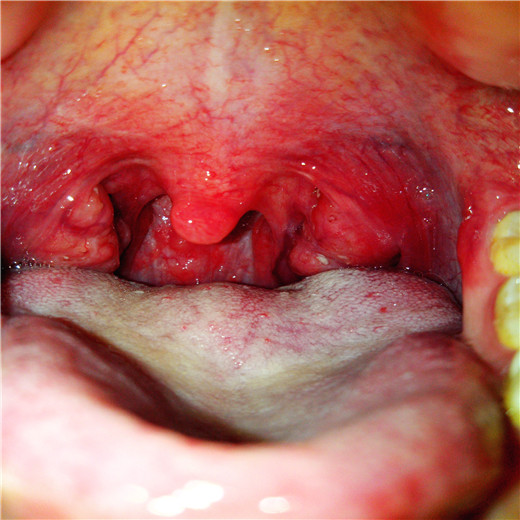

扁桃體炎圖片

扁桃體腫大